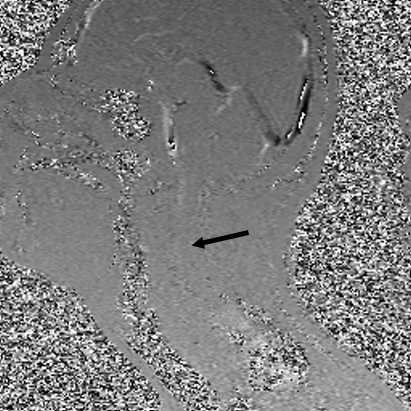

Однако, за последние десять лет в МРТ визуализации был своего рода «Ренессанс», который впервые позволил нам наблюдать за движением спинномозговой жидкости. Анимационное GIF изображение (кино-исследование движения СМЖ) является одним из тех изображений, которые использует очень продвинутую физику, чтобы показать, как СМЖ (пульсирующий темный материал) течет вокруг спинного мозга, и, на самом деле, в этом случае она немного блокируется примерно на уровне С5 (отмечено стрелкой).